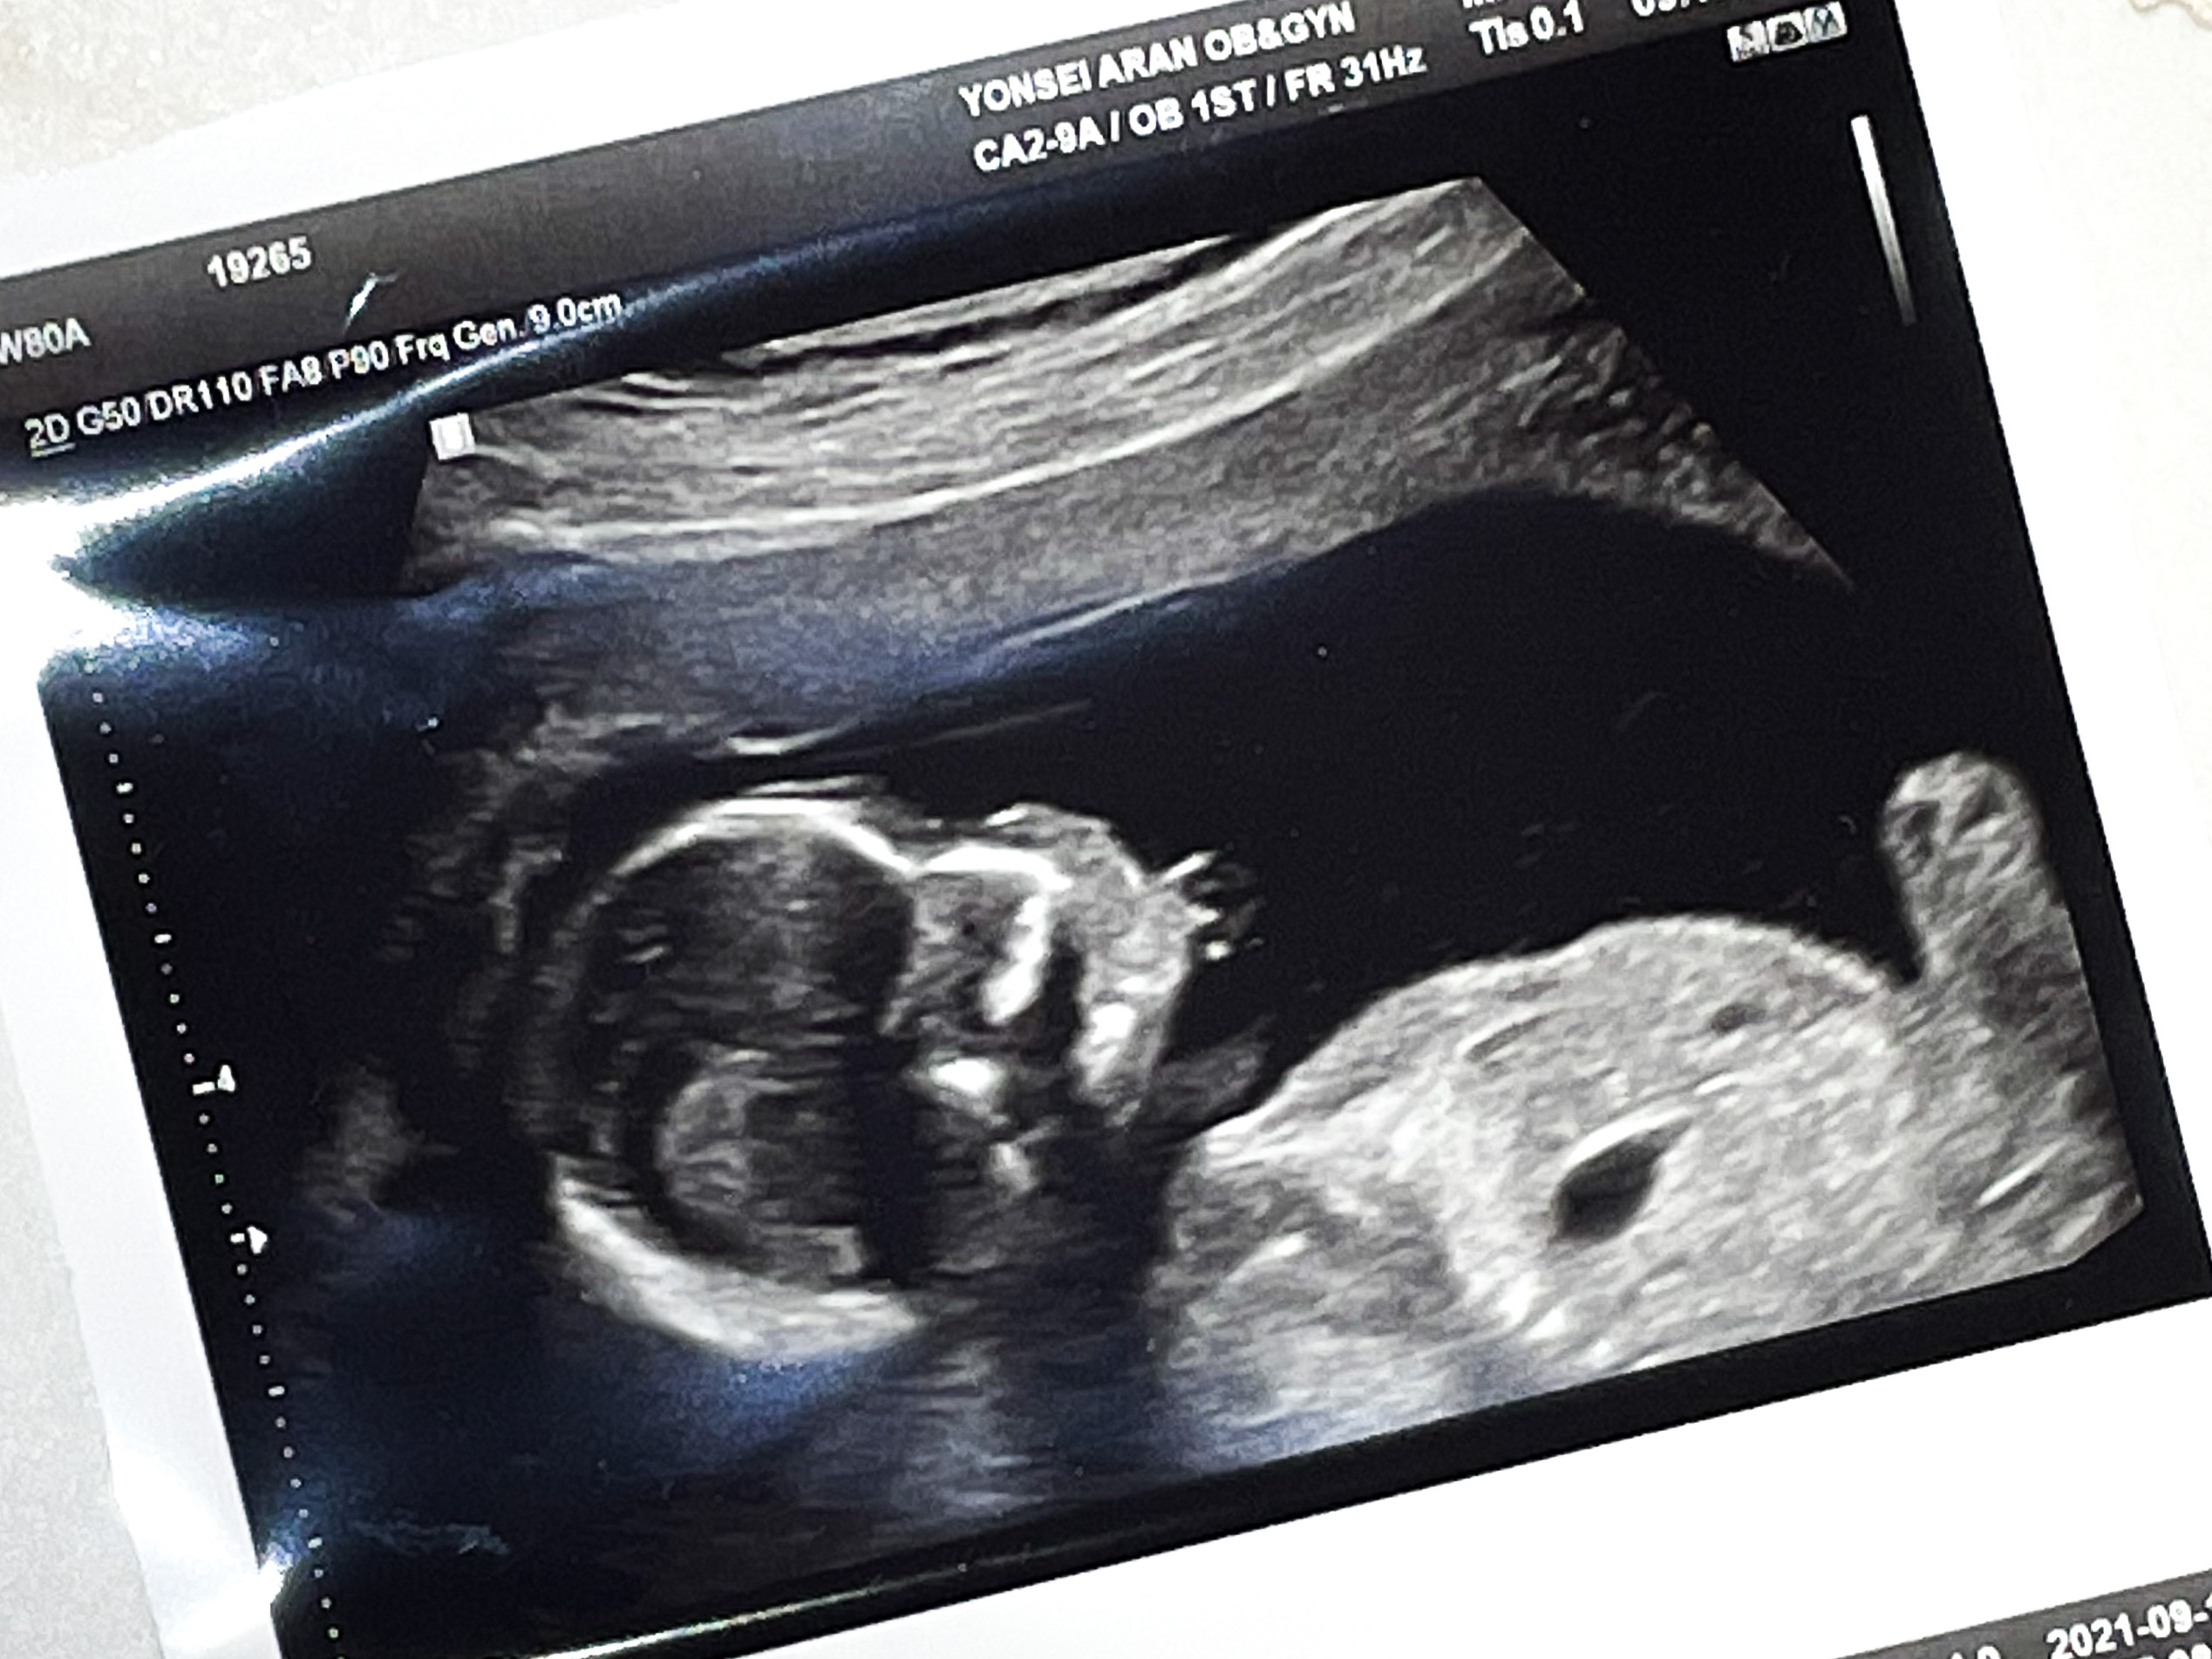

애기가 얼굴이 너무 잘보인다며 웃으셨다.

그와중에 머리는 역시 커졌고,